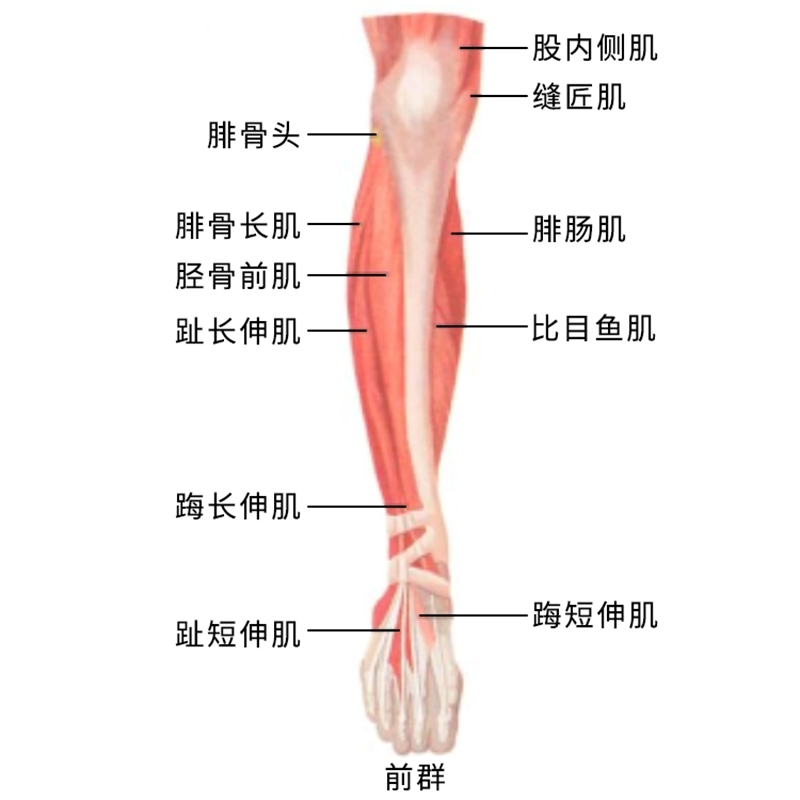

L5神经根解剖

L5神经根是腰椎间盘突出常常累及的神经根。尤其是腰4/5节段的椎间盘突出。临床可从肌力检查、感觉检查及反射检查三个方面来判断L5神经根定位的主要标志性表现。

肌力检查:

伸踇长肌(腓深神经):检查者一手固定足跟,另一手拇指放到患者踇趾甲床上,令患者背屈踇趾,检查者用力下压抵抗背屈。外加的对抗在趾间关节近端,则检查的是伸踇长肌和伸踇短肌。如果外加的对抗在趾间关节的远侧,则仅为伸踇长肌。

伸趾长、短肌(腓深神经):令患者伸直足趾,检查者拇指在趾背侧对抗,并试图向足底弯曲足趾。正常时,足趾不会被弯曲。

臀中肌(臀上皮神经):检查臀中肌,令患者侧卧,外展大腿,并施加对抗。

L5神经根定位的主要标志性表现之“足下垂”

Foot drop(足下垂):是指脚背抬高时足部无法向上抬起,导致足部处于下垂状态的情况。(足背屈肌无力)足下垂时因小腿前部肌群无力,足无法上抬,走路时病人被迫只能将患肢大幅度抬高,才能使患肢足完全离地。